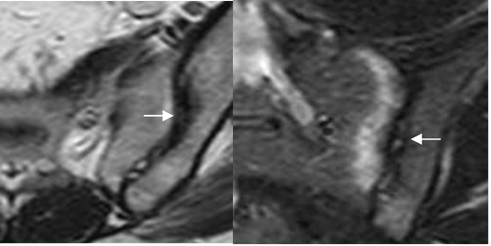

Fig 11. Sacroileitis aguda.

A: RM coronal en T1, B: RM axial en T2 y C: RM coronal en STIR. Osteitis del componente sacro derecho, de evolución aguda, hipointenso en T1 e hiperintenso en T2 y STIR. (Flechas).